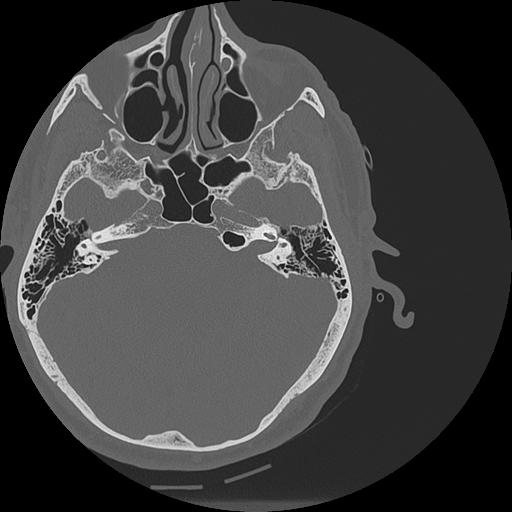

7 HUESO,,Vol,0.5,HUESO,,